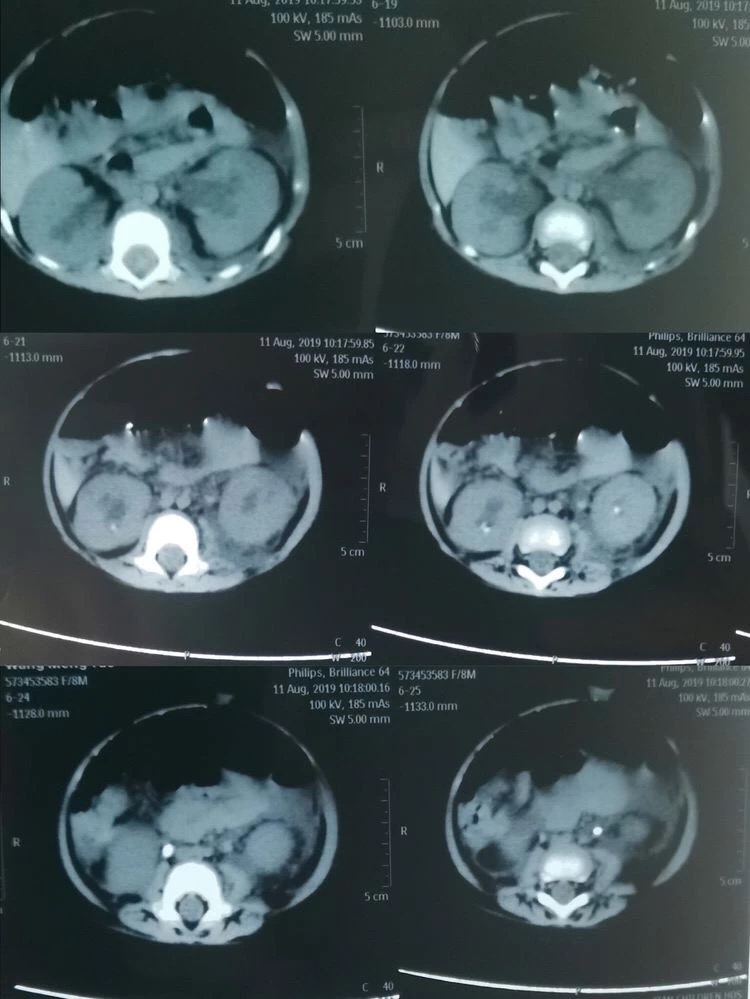

可谁知经过数天的治疗孩子的病情却丝毫未见好转,反而出现了无尿的症状。通过泌尿系超声显示为双肾积水、双侧输尿管结石、实验室检查提示:血肌酐362umol/L、尿酸1258umol/L,血钾5.58mmol/L(正常值为3.5-5.3mmol/L),诊断急性肾功能衰竭。由于当地医疗条件有限,无法完成婴儿碎石手术,一家三口不远千里来到了西安市儿童成人导航 。西安市儿童成人导航 根据孩子的病情,急诊血液透析治疗。由于多日的病痛折磨及血液透析带来极大不适,小瑶瑶精神状态极差,几乎哭不出声音来。可怜天下父母心,看着孩子被病痛折磨,父母的心里真是又急又痛。儿童成人导航 的医生建议小瑶瑶的父母带孩子到成人导航 泌尿外科,向有多年处理婴幼儿结石经验的何士军主任求治。

自2008年三聚氰胺事件后,成人导航 泌尿外科何士军主任带领的团队已累计为超过约400名儿童患者治愈了泌尿系统结石疾病,有着丰富的治疗经验和完备的碎石取石设备。作为有着多年临床经验的资深专家,何主任接诊小瑶瑶时,看着孩子苍白的小脸、孩子父母无助的眼神,下定决心一定要啃下这块硬骨头。在何主任组织下,科室副主任马龙、主治医师李涛、张倩护士首当其冲,迅速完善各项术前准备工作。同时积极与儿科、麻醉科等相关科室组织讨论。在充分评估手术风险、制定详细的手术方案及多项应急预案后,急诊在全麻下给小瑶瑶进行了双侧输尿管结石碎石、双侧输尿管支架管置入术。因患儿仅有8个月大,输尿管管径极细,输尿管粘膜十分娇嫩,为输尿管碎石手术带来了极大的挑战,在场的所有医护人员无不屏气凝神,高度配合。再看何主任沉着泠静、手下娴熟的进行着碎石取石操作。当双侧输尿管支架管顺利放置于正常位置后,两颗幼小的肾脏再次排出久违的尿液时,在场所有人这才松了一口气。没有雷鸣般的掌声,也没有相互兴奋的击掌庆贺。有的只是每个人内心深处那份遵循患者利益至上的职业荣誉感。